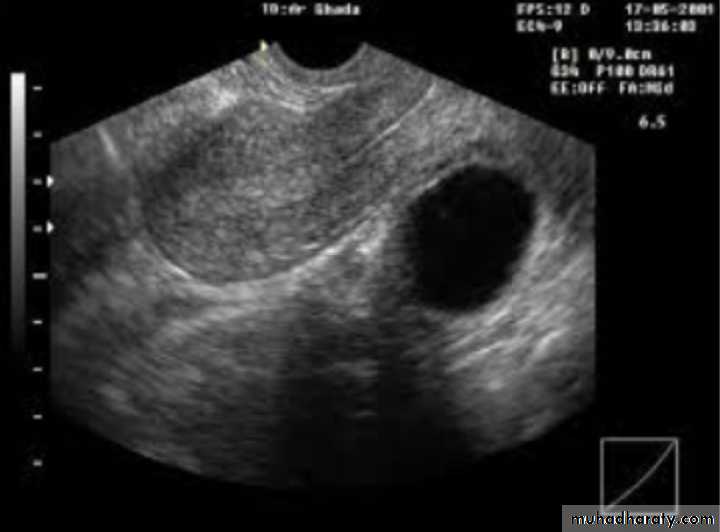

U/S:PCOS

Dx: simple ovarian cyst

Description: round regular; smooth outline ;single echogenicity ;not contain blood ,contain only fluid

Tx:

-small and asymptomatic : conservative tx ;COCP

-large and symptomatic: surgical removal of cyst